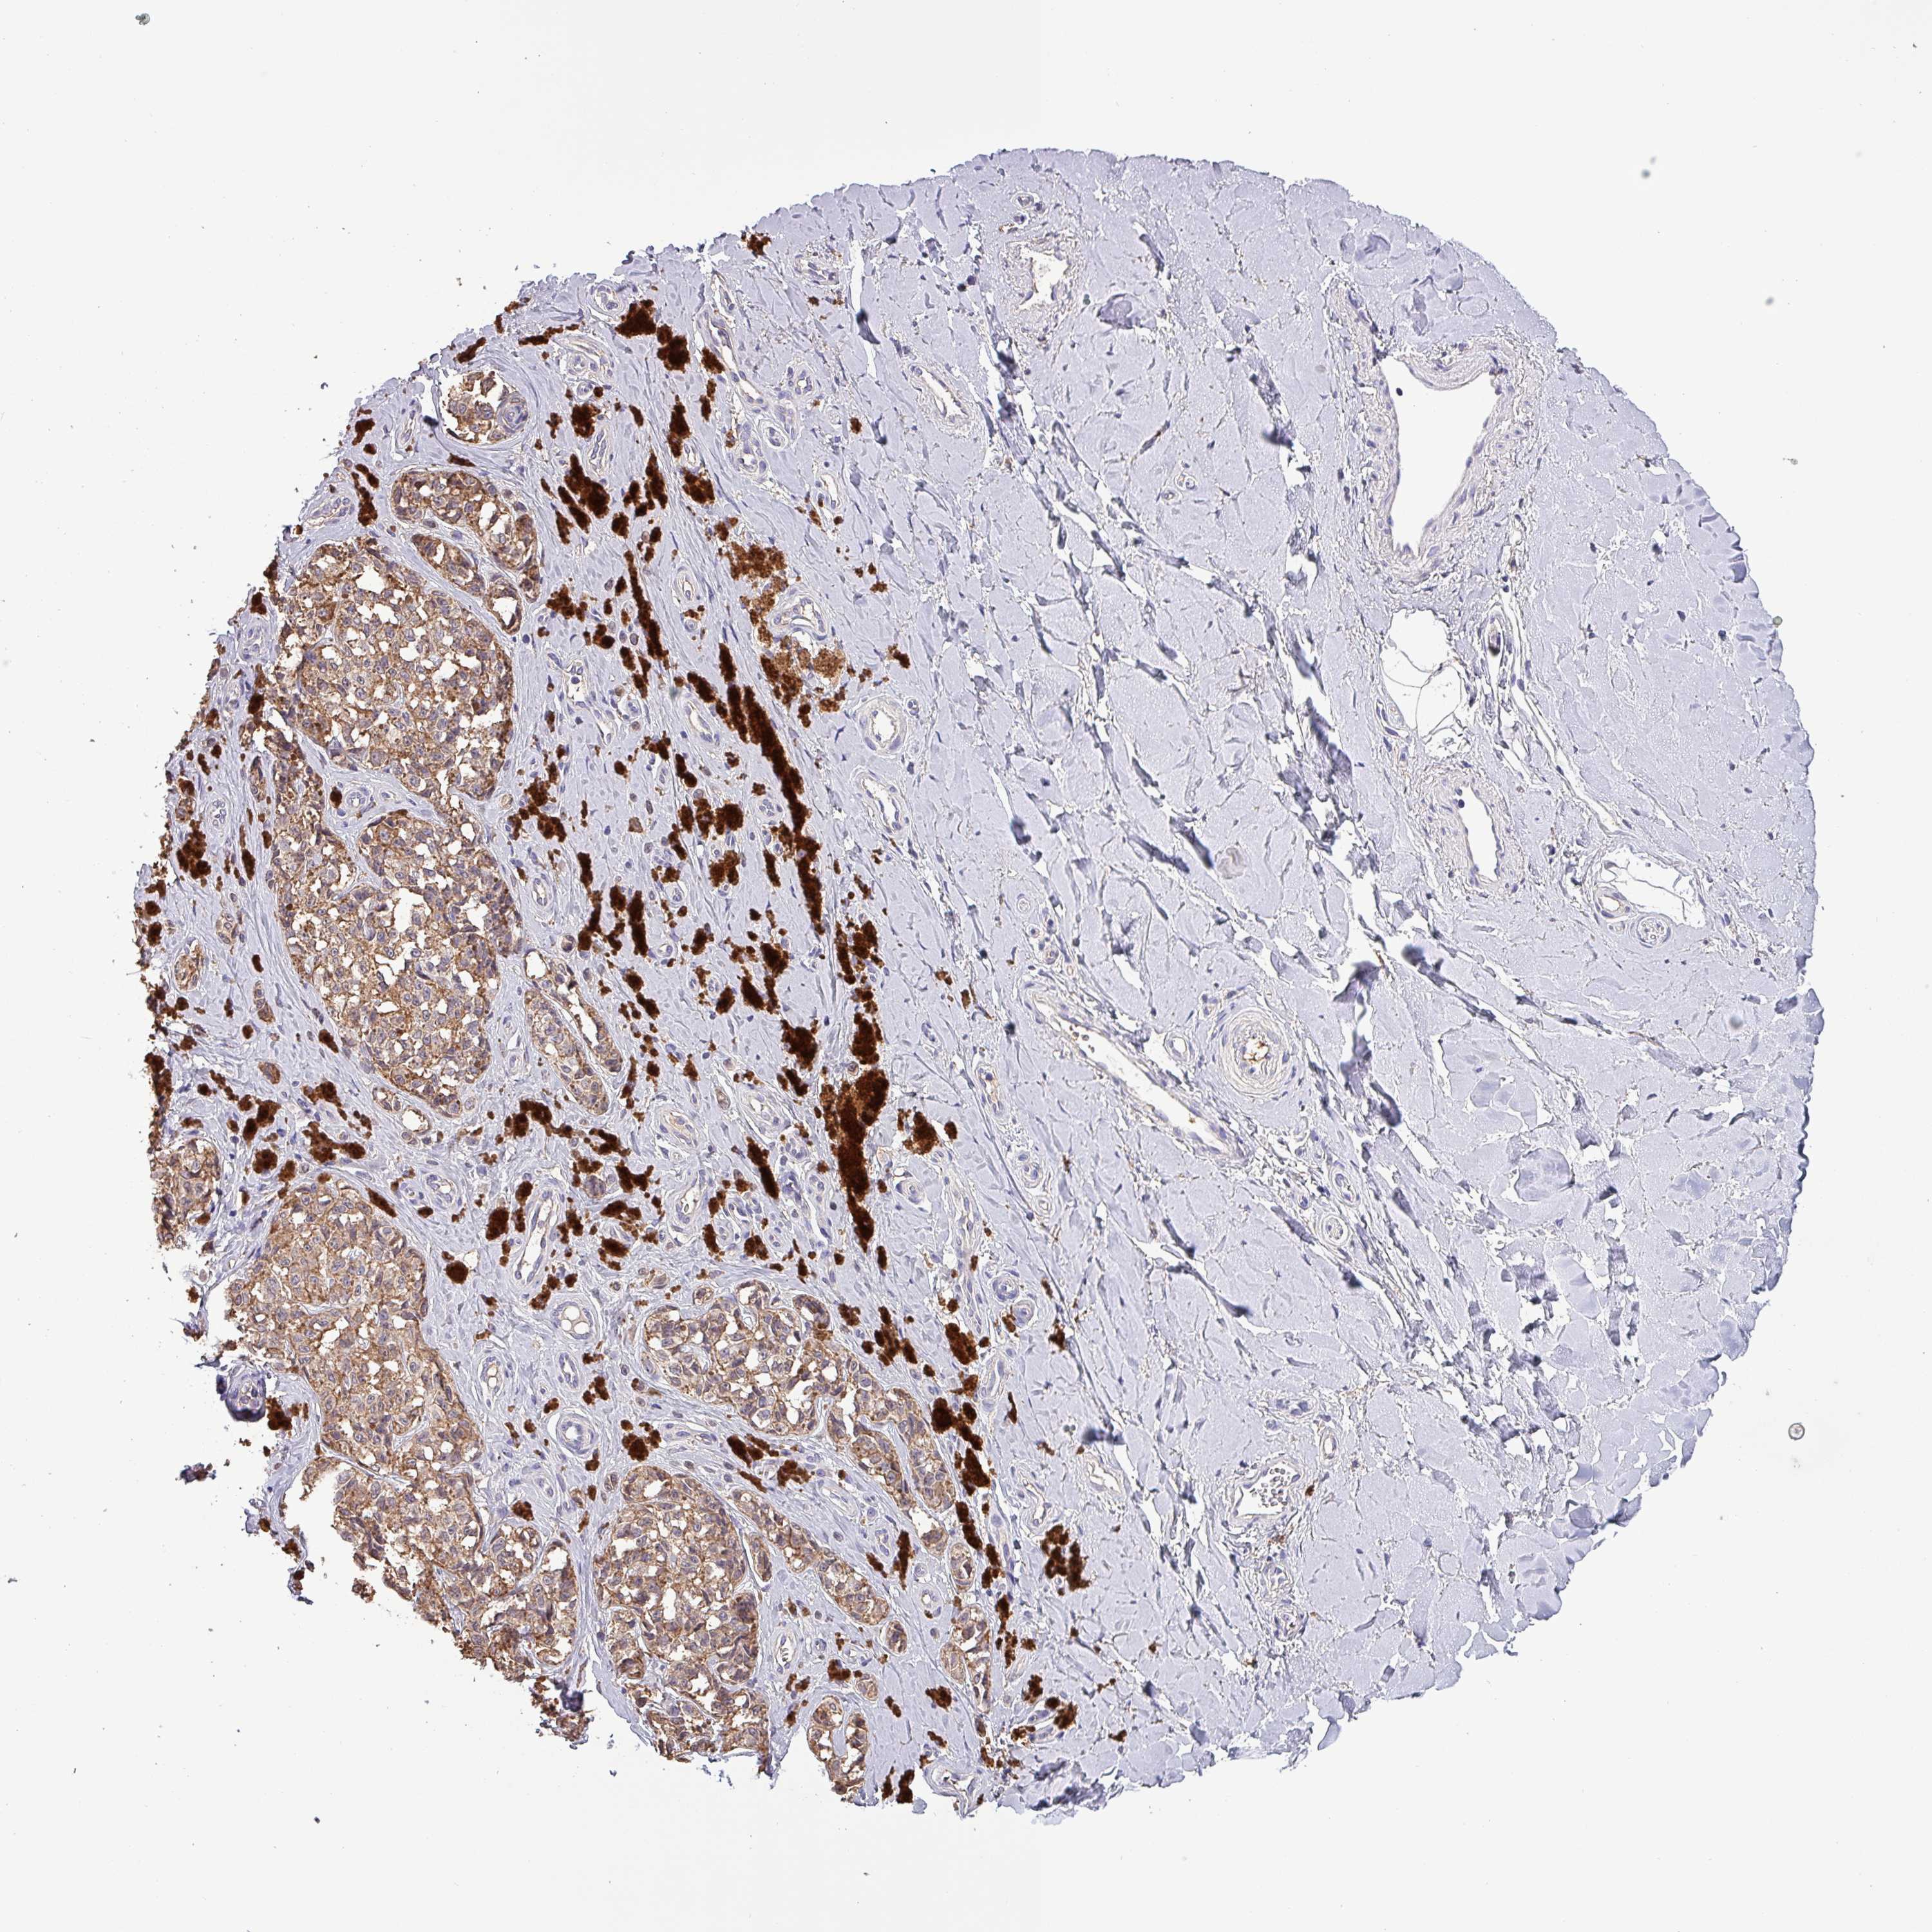

MELANOMA - Protein expressioni

A mouse-over function shows sample information and annotation data. Click on an image to view it in a full screen mode. Samples can be filtered based on level of antibody staining by selecting one or several of the following categories: high, medium, low and not detected. The assay and annotation is described here.

Note that samples used for immunohistochemistry by the Human Protein Atlas do not correspond to samples in the TCGA dataset.

Antibody stainingi

Antibody staining in the annotated cell types in the current human tissue is reported as not detected, low, medium, or high, based on conventional immunohistochemistry profiling in selected tissues. This score is based on the combination of the staining intensity and fraction of stained cells.

Each image is clickable and will lead to virtual microscopy that enables deeper exploration of all samples and also displays staining intensity scores, fraction scores and subcellular localization as well as patient and tissue information for each sample.

Antibody HPA045402

Staining

High

Medium

Low

Not detected

Intensity

Strong

Moderate

Weak

Negative

Quantity

>75%

75%-25%

<25%

None

Location

Nuclear

Cytoplasmic/membranous

Cytoplasmic/membranous,nuclear

Malignant melanoma, NOS

Malignant melanoma, Metastatic site